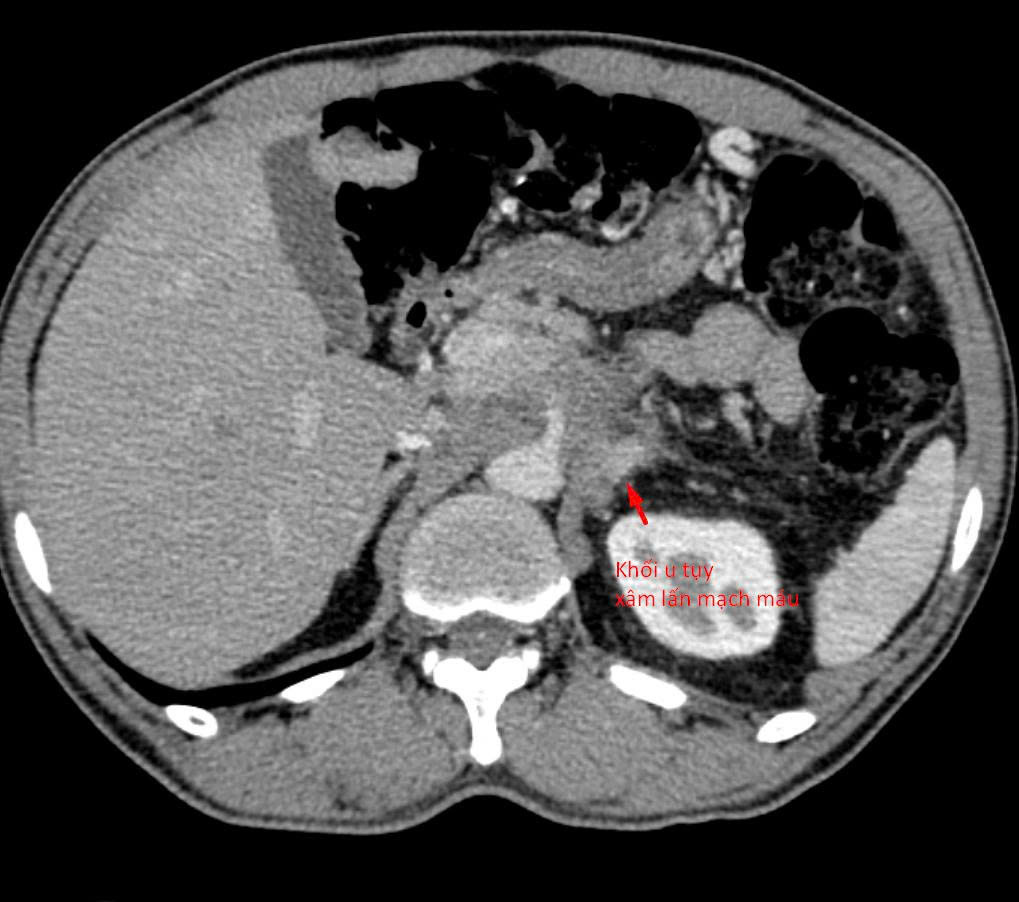

Bệnh nhân 64 tuổi (tại Hà Nội) có khối u tụy xâm lấn mạch máu được chẩn đoán tại nhiều bệnh viện khác nhau. Tuy nhiên, do khối u nằm ở vị trí đặc biệt phức tạp, áp sát nhiều cấu trúc nguy hiểm, các bác sĩ chưa thể tiến hành sinh thiết để xác định mô bệnh học – bước then chốt quyết định hướng điều trị ung thư.

Sau khi tiếp nhận bệnh nhân, các bác sĩ đã tiến hành đánh giá lại toàn bộ cấu trúc giải phẫu và đường tiếp cận khối u. Hầu hết các hướng sinh thiết thông thường đều không khả thi do nguy cơ tổn thương mạch máu lớn và các tạng quan trọng.

“Chúng tôi chỉ còn một ‘khe cửa hẹp’ duy nhất: tiếp cận từ phía sau, xuyên qua khoảng giữa cột sống và thận. Đây là đường vào rất khó, rủi ro cao và đòi hỏi kỹ thuật can thiệp cực kỳ tinh vi”, bác sĩ Giang chia sẻ.

Dưới hướng dẫn của CT đa dãy độ phân giải cao, mũi kim sinh thiết được đưa chính xác qua khe an toàn duy nhất, tiếp cận khối u và lấy mẫu bệnh phẩm thành công. Thủ thuật diễn ra an toàn, không ghi nhận biến chứng, mẫu mô đạt yêu cầu để phục vụ chẩn đoán.